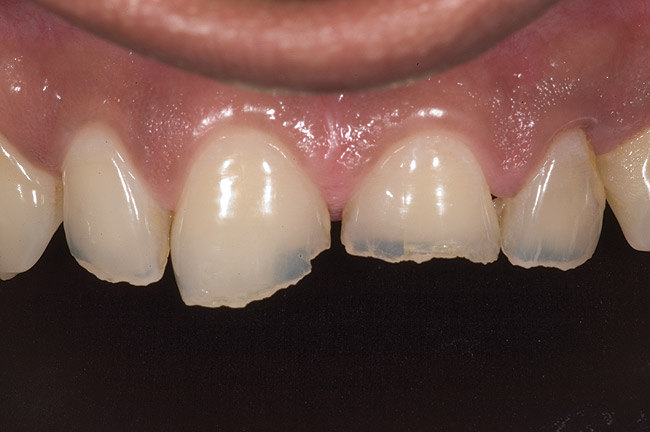

Figure 14  Postoperative smile.

Figure 14

Figure 15  Maximum intercuspation (MIP) after restoration of the lost palatal anatomy.

Figure 15

Figure 16  1:2 right lateral view; posteriors discluded in MIP.

Figure 16

Figure 17  1:2 left lateral view; posteriors discluded in MIP.

Figure 17

Figure 18  1:1 view of restored palatal surfaces with nanofilled resin.

Table 1